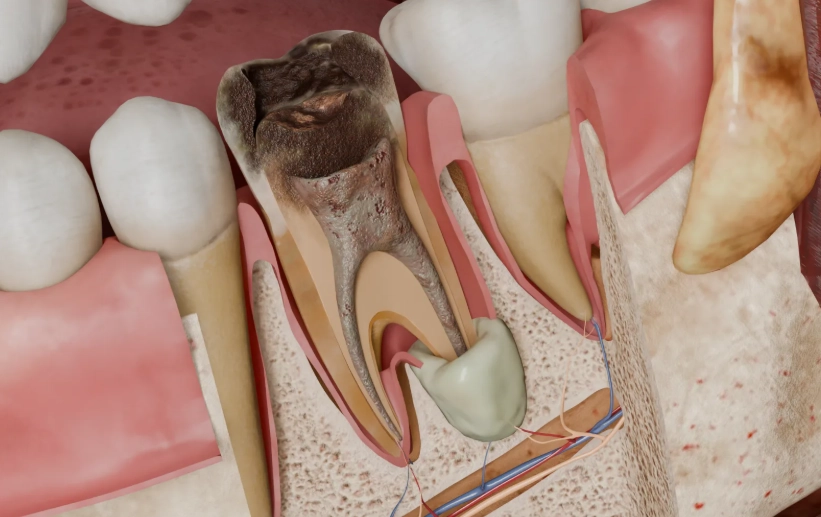

What Your Doctor Sees in Your Periapical Abscess CT Scan

Let's break down the specific things your endodontist is hunting for when they analyze your scan. It's more than just "yep, there's an infection."

- Lesion Characterization: Is the boundary of the abscess well-defined (suggesting a slower, chronic process) or fuzzy and spreading (suggesting an aggressive, acute infection)? This influences treatment urgency.

- Bone Loss Dimensions: The exact height, width, and depth of the bone destroyed. This is crucial for prognosis—can the bone heal back after treatment?

- Anatomical Relationships: This is the big one. The scan maps exactly how close the abscess and tooth roots are to vital neighbors. For upper back teeth, how much bone is left between the root tip and the sinus floor? For lower teeth, is the abscess or root tip actually touching the nerve canal? The American Association of Endodontists (AAE) has clear guidelines on using CBCT for this precise mapping, which you can read about in their Guide to Clinical Endodontics.

- Root Canal Anatomy: Surprise extra canals, severe curves, or calcified (blocked) canals are all clearly visible. No more guesswork during the root canal procedure.

- Root Fractures: A vertical crack in the root is often a death sentence for a tooth. 2D X-rays miss most of them. A CT scan can frequently detect these fractures, saving you from a doomed treatment.